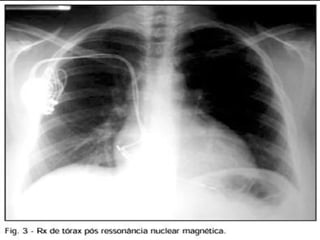

Desde 2010, já existem mercado brasileiro os

marca-passos MRI, que são compatíveis com

ressonância magnética.

• Esses marca-passos suportam campos eletromagnéticos intensos

e, por isso, permitem uma vida praticamente normal.

• Hoje em dia, a ressonância magnética é um exame que será

necessário para a maioria das pessoas: para doenças da idade

(coluna, AVC, quadril, doenças neuro-degenerativas), e também

para doenças dos jovens (lesões de joelho, ombro, quadril).

• É função médico cirurgião cardíaco que for fazer o implante do

marca-passo, solicitar ao convênio a prótese que traz essa nova

tecnologia.

Desde 2010, jáexistem mercado brasileiro os marca-passos MRI, que são compatíveis com ressonância magnética. TELEFONE RESSONÂNCIA MAGNÉTICA FORNO MICROONDAS

• Esses marca-passossuportam campos eletromagnéticos intensos e, por isso, permitem uma vida praticamente normal. • Hoje em dia, a ressonância magnética é um exame que será necessário para a maioria das pessoas: para doenças da idade (coluna, AVC, quadril, doenças neuro-degenerativas), e também para doenças dos jovens (lesões de joelho, ombro, quadril). • É função médico cirurgião cardíaco que for fazer o implante do marca-passo, solicitar ao convênio a prótese que traz essa nova tecnologia. INTERESSANTE !